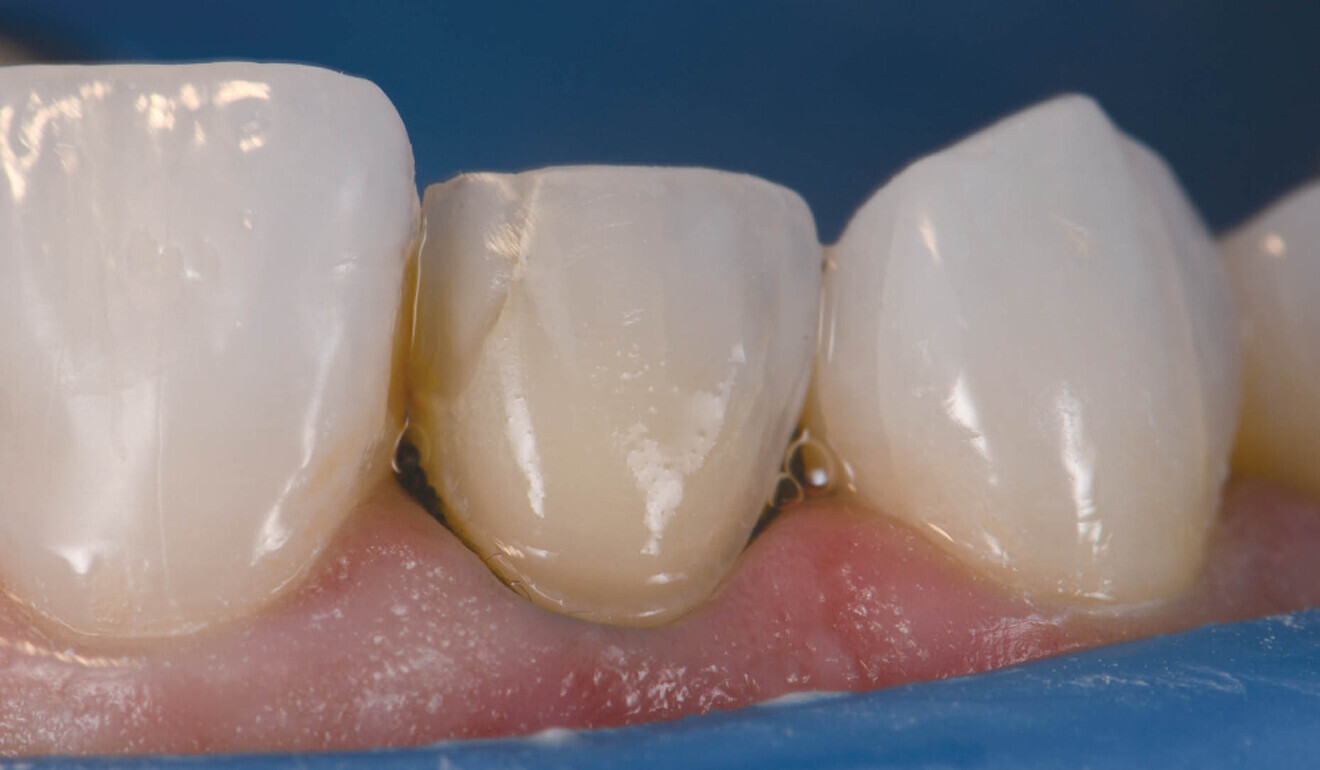

Final result of a veneer cementation procedure with polarised photography on reassessment. (All images: Clarence Tam)

The cement was rendered into a gel state, which facilitated clumping or en masse removal of cement, requiring minimal clean-up (Fig. 7). The margins were coated using a clear glycerine gel prior to final polymerisation to eliminate the oxygen inhibition layer (Fig. 8). The margins were finished and polished to a high shine and the occlusion of the restorations verified. The postoperative views showed excellent aesthetic marginal integration (Fig. 9). On polarised photograph reassessment, the restorations were found to be well integrated into the new smile aesthetically and functionally (Fig. 10), and aesthetic augmentation of tooth #23 to match the contralateral canine was awaited.

Fig. 10: Final result with polarised photography on reassessment.